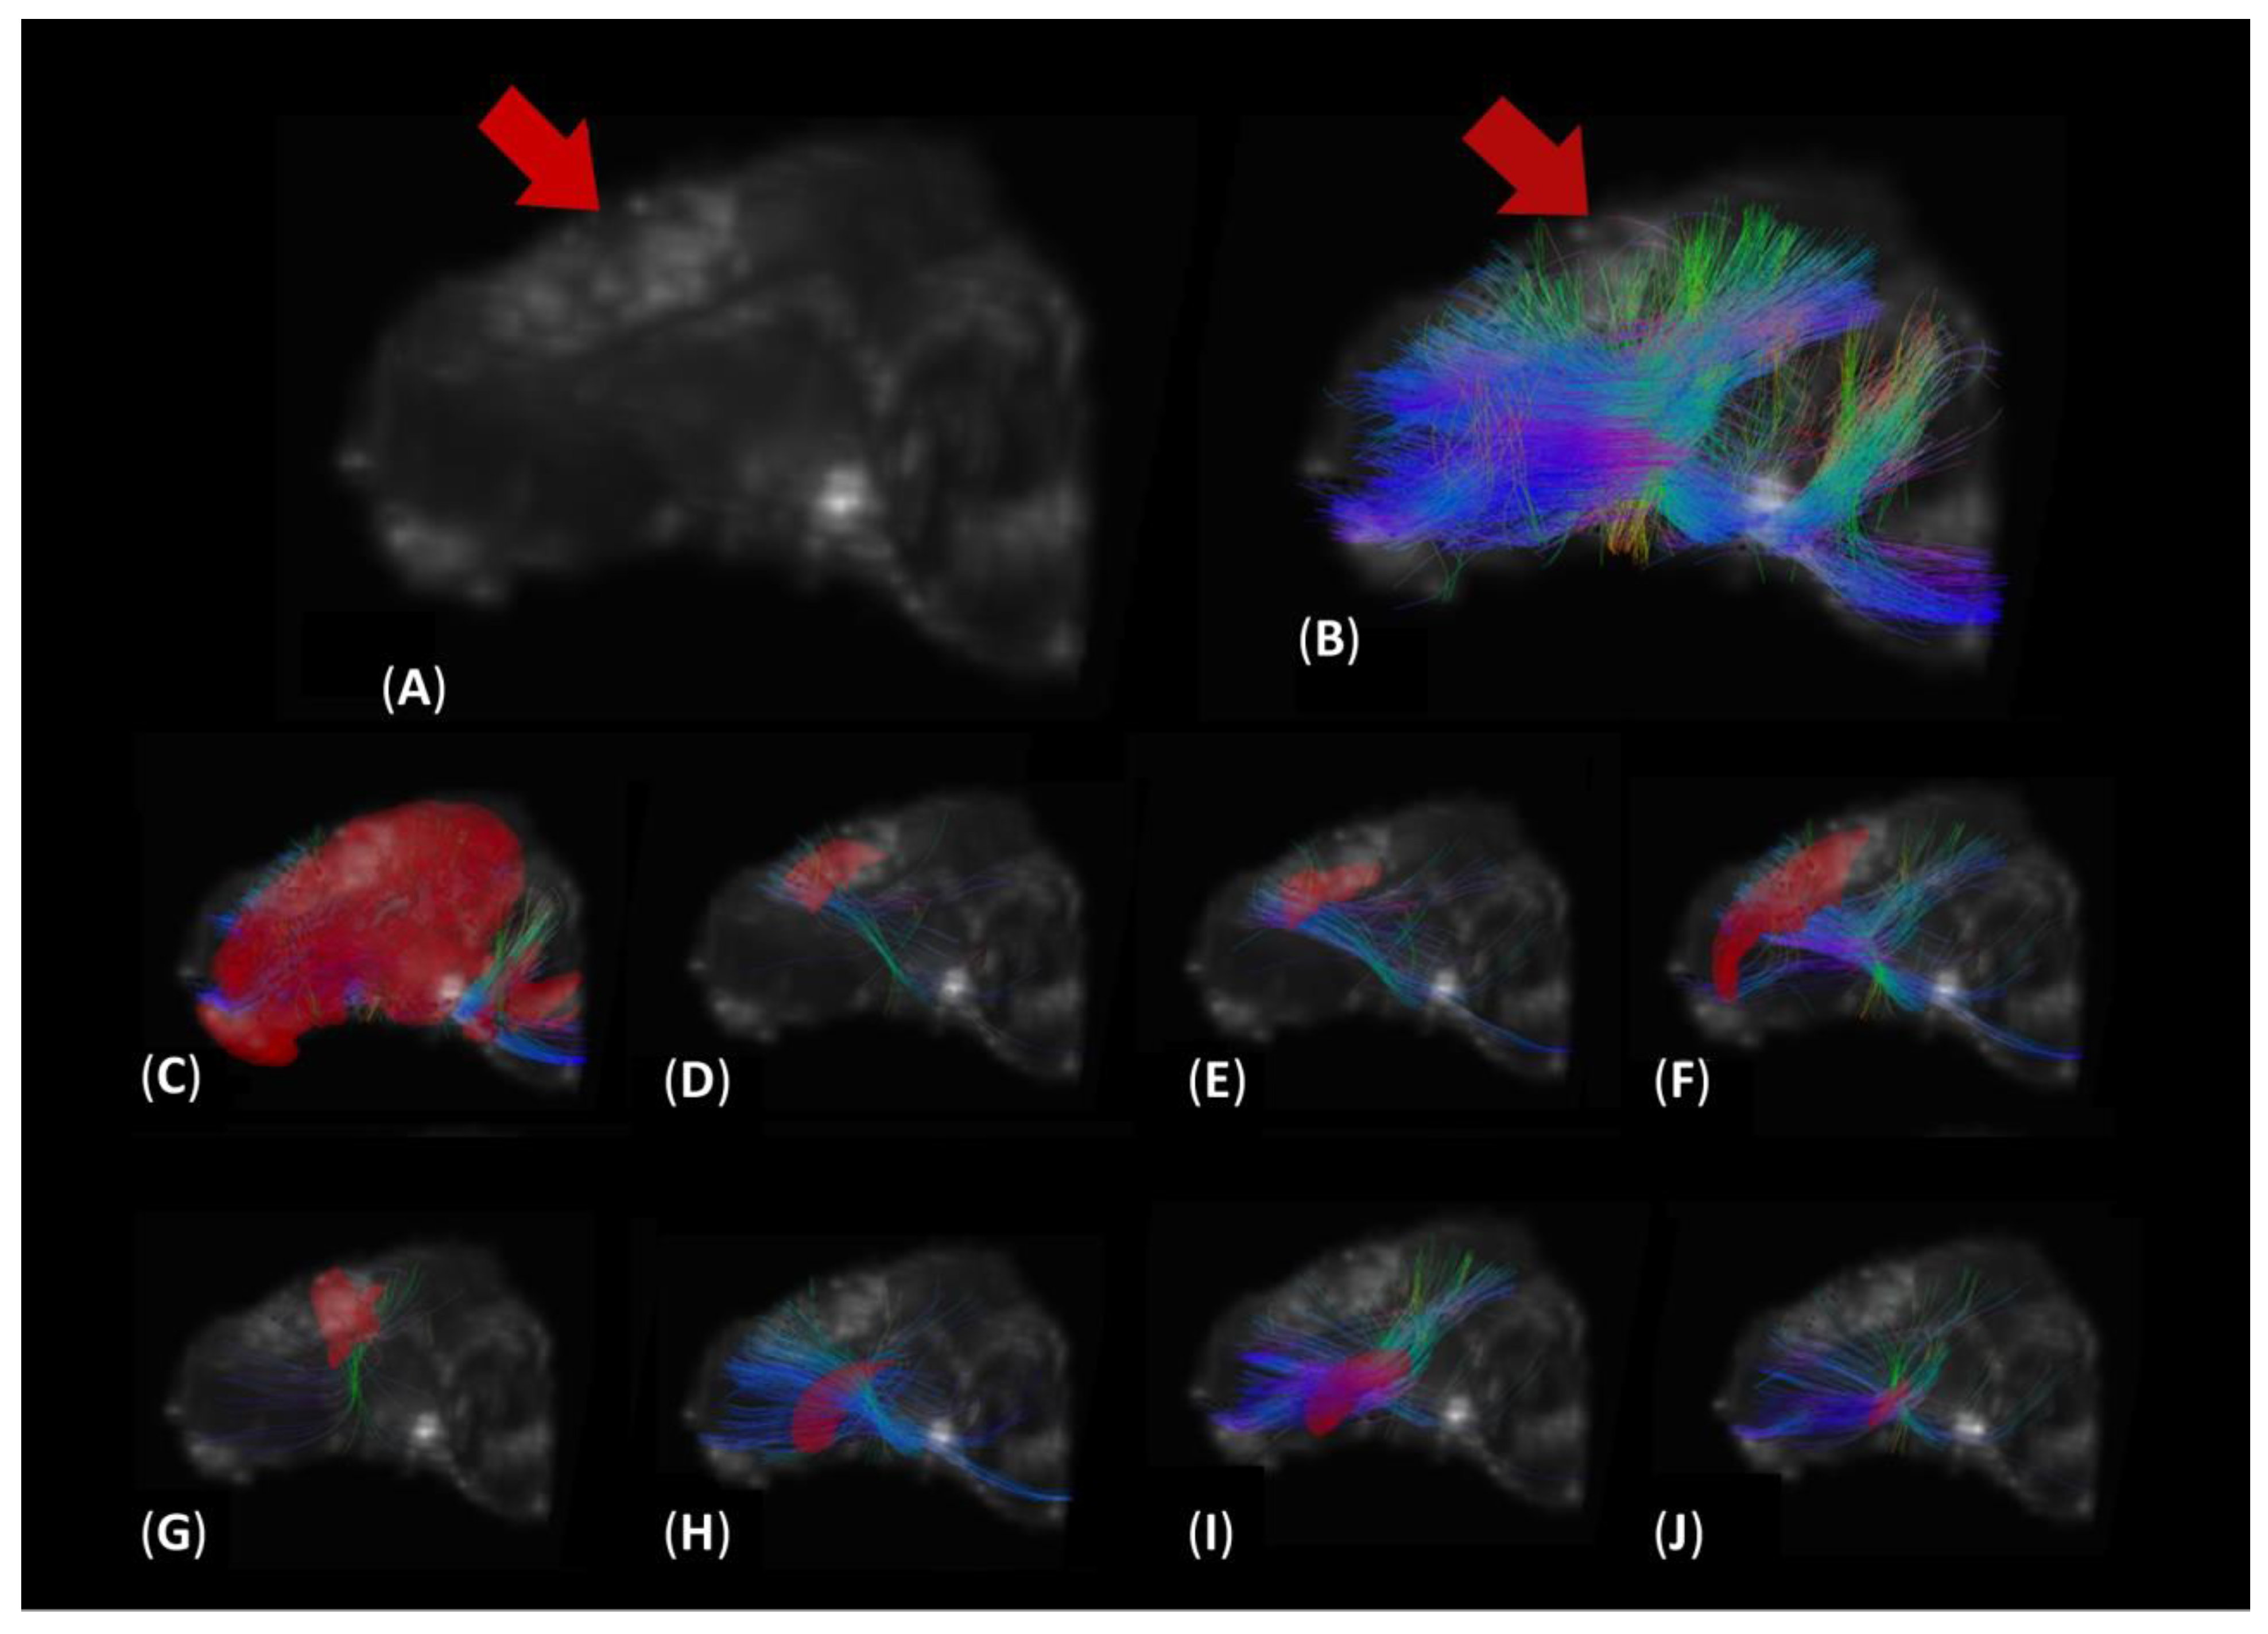

3.2. DTI Tractography Reveals Increased Diffusion in Fibers Intersecting Both Ipsilateral and Contralateral Motor Function-Related Brain Structures